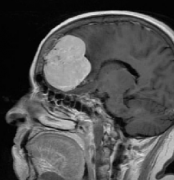

脑膜瘤是从覆盖大脑和脊髓的膜(“脑膜”)发展而来的脑瘤。大多数脑膜瘤是良性的。脑膜瘤严重吗?脑膜瘤不做手术可以吗...

脑膜瘤3Cm严重吗?怎么治疗比较好?脑膜瘤是较常见的脑肿瘤——约占全部脑肿瘤的30%——大多数是可以治疗的。事实上,这些肿瘤大多数可以通过手术切除,许多不会复发。脑膜瘤起...

脑膜瘤3Cm严重吗? 脑膜瘤手术 后多久恢复? 脑膜瘤(Meningiomas)是一种常见的颅内肿瘤,在颅内肿瘤中占二位,是起源于脑膜及脑膜间隙的衍生物。大多数脑膜瘤属于良性肿瘤,生...